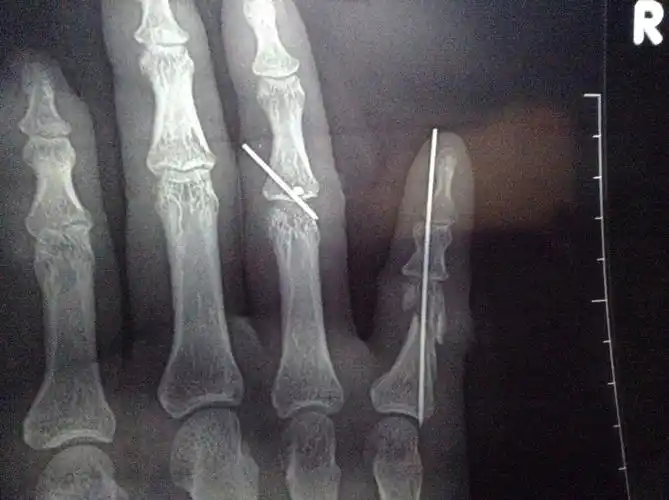

克氏针过两天就可以拔了,然后到公司私了大概能赔

temporary transarticular k-wire fixation of critica